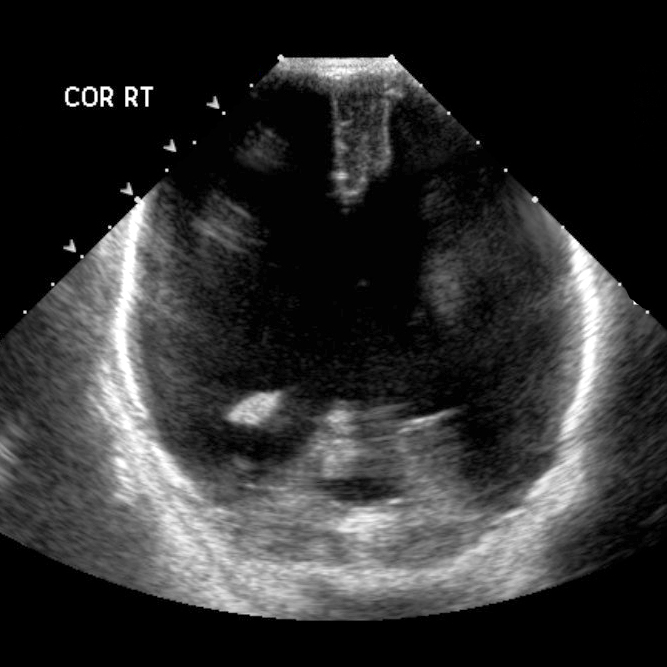

Hydranencephaly is a rare encephalopathy that occurs in-utero. It is characterised by destruction of the cerebral hemispheres which are transformed into a membranous sac containing cerebrospinal fluid and the remnants of cortex and white matter 1. Porencephaly is considered a less severe degree of the same pathology 10

There is marked enlargement of fluid spaces with little if any overlying cerebral parenchyma except for the posterior fossa and para medial location along the falx.

The posterior fossa structures are inferiorly displaced and the fourth ventricle is not well seen. Higher cuts demonstrate marked cerebral destruction of both cerebral hemispheres predominately in the distribution mid cerebral arteries with minimal residual tissue identified both anteriorly and posteriorly. The anterior fontanelle is bulging.

This case demonstrates typical CT and ultrasound appearances of hydranencephaly, which is in almost all cases not compatible with significant post natal survival.